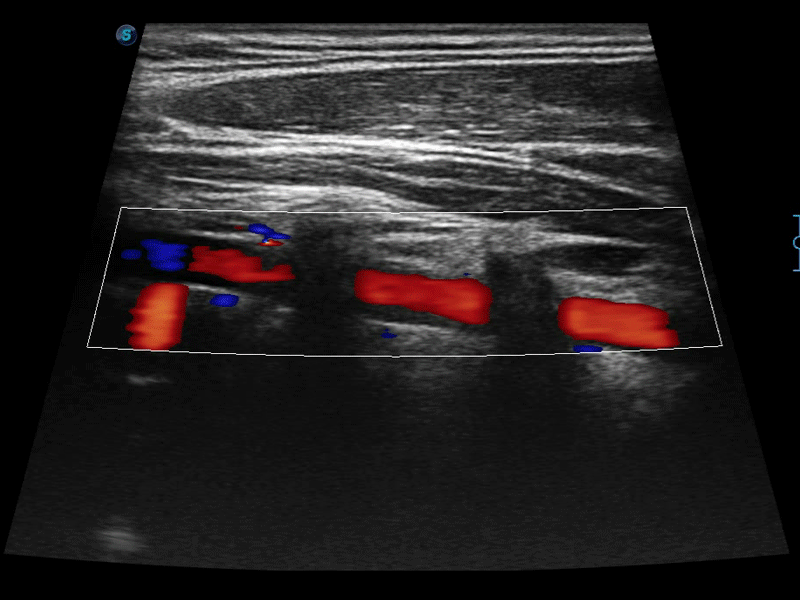

• SR Flow高分辨率血流成像技术

高分辨率血流成像技术提高了对低速血流信号的检测能力。在提高空间分辨率的同时,也克服了血流外溢现象,为用户提供更加真实的血流动力学信息。

• 实时宽景成像技术

通过色彩血流和实时宽景相结合,可观察到完整的静脉或动脉的血流,方便医生检查。实时扫查过程中,如有任何操作失误也可以很容易地进行回扫擦除,而不会中断扫查。